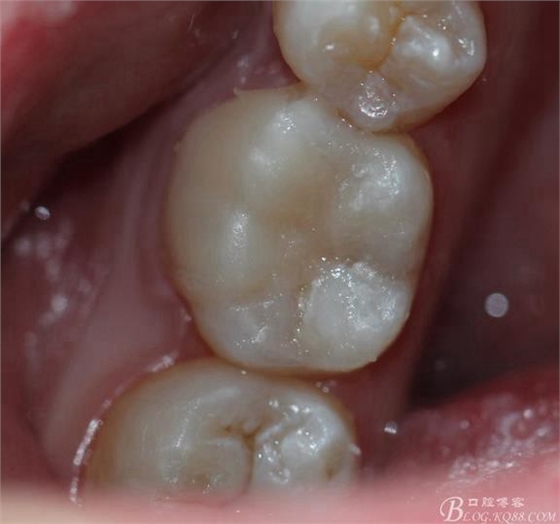

主訴:雙側(cè)下后牙疼痛一月余

病史:近一個月雙側(cè)下后牙疼痛,自發(fā)性 陣發(fā)性鈍痛,進食嵌塞加重,求診

查:雙側(cè)下6頰HE面齲壞 探診疼痛 冷熱刺激 遲反應(yīng)疼痛 叩診(-)頰側(cè)齲壞平齦

X線:雙側(cè)下6 齲壞已接近髓腔

診斷:雙側(cè)下6 慢性牙髓炎

治療方案:雙側(cè)RCT+CAD-CAM

這里我單做右側(cè)的詳細步驟